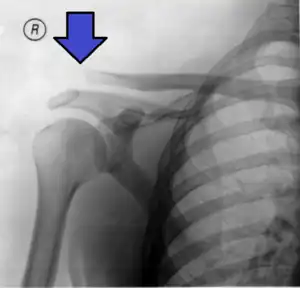

An Xray showing a separated shoulder. Notice the separation between the end of the collarbone and the scapula.

A separated shoulder, also known as acromioclavicular joint injury, is a common injury to the acromioclavicular joint.[2] The AC joint is located at the outer end of the clavicle where it attaches to the acromion of the scapula.[2] Symptoms include pain which may make it difficult to move the shoulder and often a deformity.[2][1]

It is most commonly due to a fall onto the front and upper part of the shoulder when the arm is by the side.[2] They are classified as type I, II, III, IV, V, or VI with the higher the number the more severe the injury.[2] Diagnosis is typically based on physical examination and X-rays.[2] In type I and II injuries there is minimal deformity while in a type III injury the deformity resolves upon lifting the arm upwards.[2] In type IV, V, and VI the deformity does not resolve with lifting the arm.[2]

X-ray indicates a separated shoulder when the acromioclavicular joint space is widened (it is normally 5 to 8 mm),[11]it can be classified into 6 types.